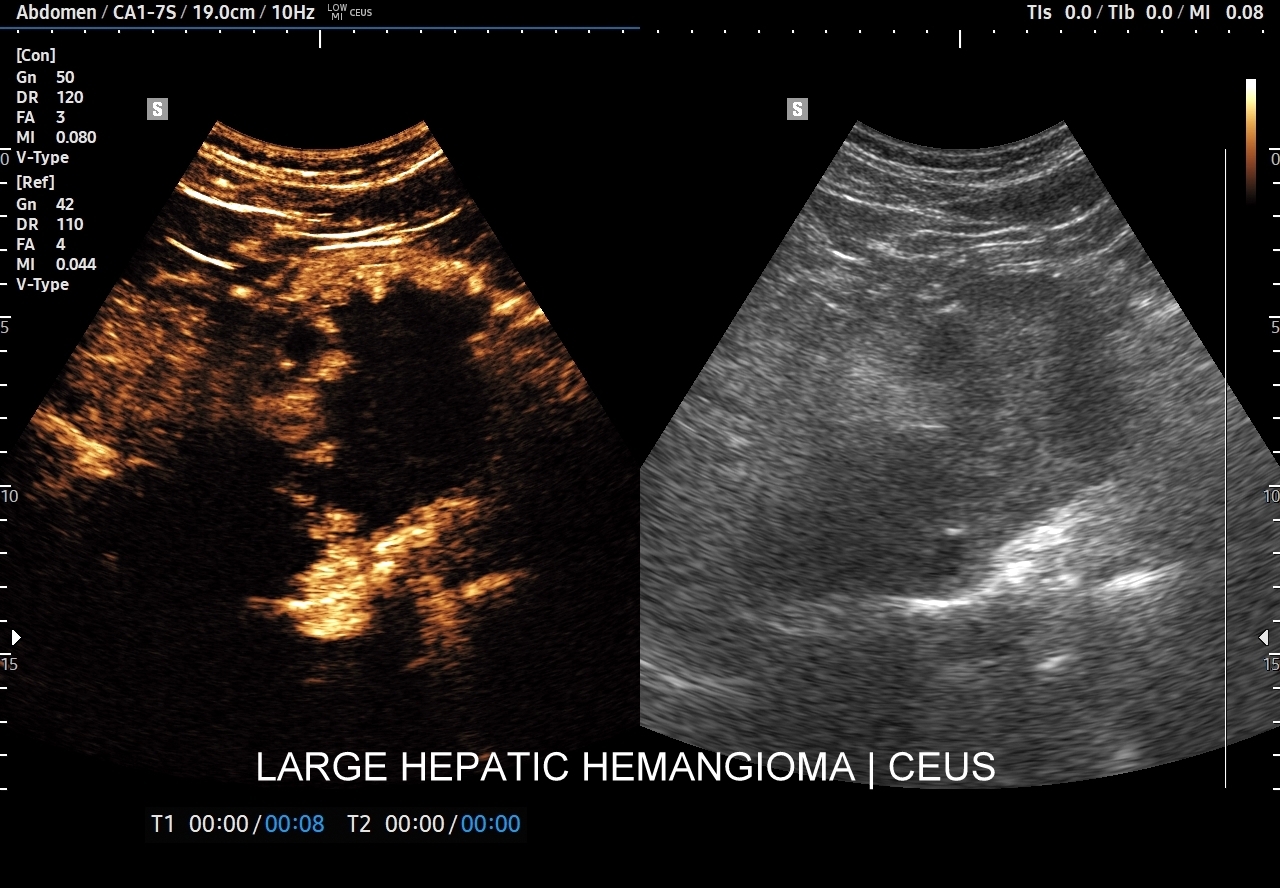

Najbardziej charakterystyczną cechą naczyniaka wątroby w badaniu CEUS jest jego wypełnianie w postaci guzkowej (ang. peripheral nodular enhancement) od obwodu ku centrum zmiany (ang. centripetal). Szybkość wypełniania bywa różnorodna, może być powolna lub szybka. W przypadku szybkiego wypełniania (tzw. flash-filling), w celu wykazania charakterystycznego centrypetalnego wypełniania niezbędna może być postprocessing’owa analiza poklatkowa zapisanego nagrania badania. W fazie późnej naczyniak wątroby pozostaje izowzmocniony lub hyperwzmocniony w stosunku do natywnego miąższu wątroby.

W przypadku dużych naczyniaków obszary, które uległy wykrzepianiu pozostają awaskularne przez wszystkie fazy badania CEUS, tj. nie wypełniają się kontrastem (nonenhancing). W przeciwieństwie do powyższego konstelacja, w której to w fazie wczesnej pojawia się wzmocnienie, a następnie w fazie wrotnej lub późnej ulega wypłukaniu (hypoenhancement) świadczy o cechach złośliwych diagnozowanej zmiany ogniskowej w wątrobie i wyklucza rozpoznanie naczyniaka.